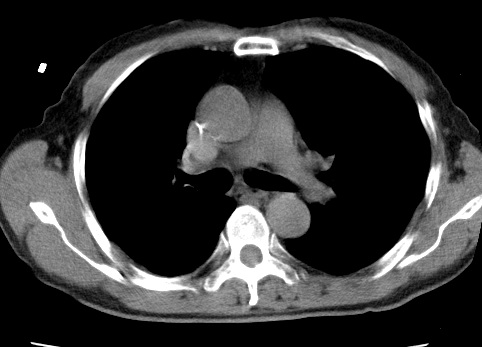

标题: CT24032:男65岁,咳嗽,吸烟20余年,无发热,咳痰 [打印本页]

标题: CT24032:男65岁,咳嗽,吸烟20余年,无发热,咳痰

考虑右肺中叶不张,请大家发表意见

右肺中叶不张、肺门轮廓增大,占位不除外;建议增强,必要时支气管镜详查。

右肺中叶支气管闭塞,中叶肺不张,右侧肺门见肿块影。中心型肺癌的可能大。建议支气管镜检查。

右中叶体积明显缩小,且其支气管未显示,先考虑:中心型肺癌班右中叶肺不张。

建议:支气管镜检查。

右肺门旁类圆形肿块影,右肺中叶不张,建议纤支镜检查。

1右肺门旁类圆形肿块影,右肺中叶不张,建议纤支镜检查

2右侧胸膜增厚,右侧叶间胸膜区钙化

3右肺下叶小囊状透亮影考虑肺气肿